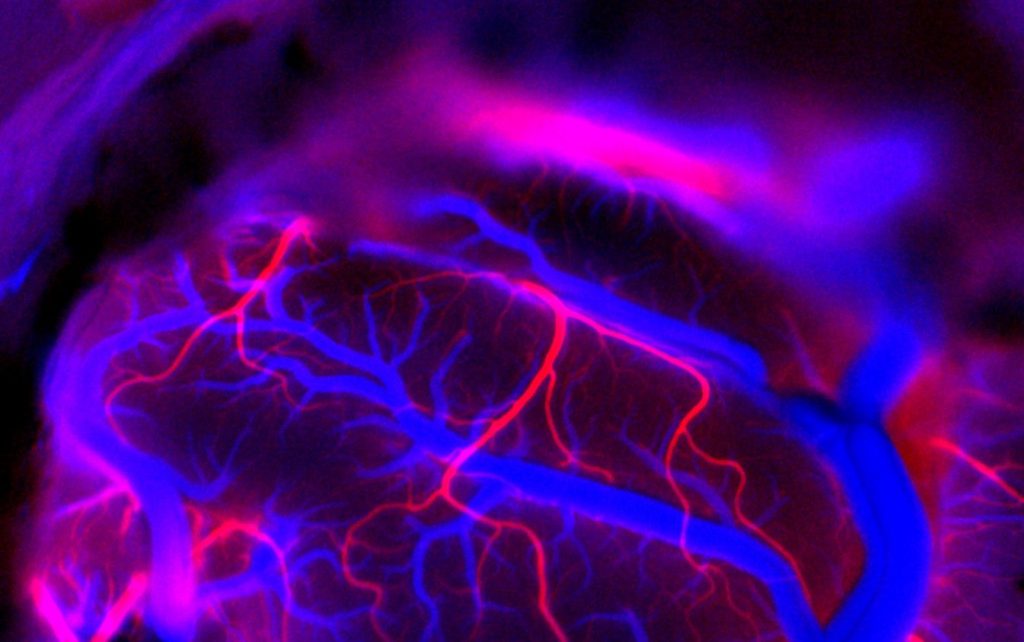

Silvestro Micera. Neuralink vuole creare una nuova versione di brain-computer interface: dispositivi impiantati nella corteccia cerebrale per estrarre segnali (in particolare dalla corteccia motoria primaria) e per permettere alle persone con gravi disabilità di controllare i dispositivi esterni e, potenzialmente, con bypass nella lesione anche tornare a muovere i propri arti.

Silvestro Micera. La tecnologia è solidissima per questo ha avuto l’autorizzazione dalla Food and Drug Administration (FDA), l’agenzia federale degli Stati Uniti che si occupa di farmaci e dispositivi medici, per fare impianti sull’essere umano. Ha due vantaggi questa tecnologia, da dimostrare poi con i risultati: è meno invasiva rispetto agli impianti tradizionali perché il sistema robotico consente di impiantare gli elettrodi in modo più preciso. E non centinaia di elettrodi, come fino a ieri, ma migliaia. Il che vuol dire avere molti più segnali-informazioni sul paziente ed estrarre più comandi sofisticati.